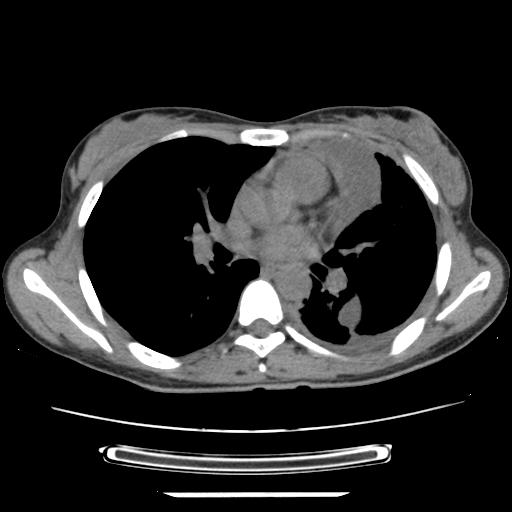

标题: CT21561:外院胸片提示胸腔积液,行CT检查。 [打印本页]

女,29岁,胸部不适,在外院胸片提示胸腔积液,到我院ct检查。

纵膈窗

1、左侧包裹性积液伴叶间积液 2、右肺多发结节考虑增殖结节

左侧纵隔胸膜包裹性积液、左侧胸腔积液、胸膜肥厚粘莲,考虑结核性胸膜炎

左肺上叶不张,左侧胸水,叶间裂积液,纵隔淋巴结,脾脏钙化,考虑左肺上叶支气管内膜结核,结核性胸膜炎,脾结核

支持两肺继发性肺结核,左侧胸膜腔包裹性积液、胸膜肥厚,脾内多发钙化(结核钙化)。

右肺多发结节。左胸腔多发包裹性积液。